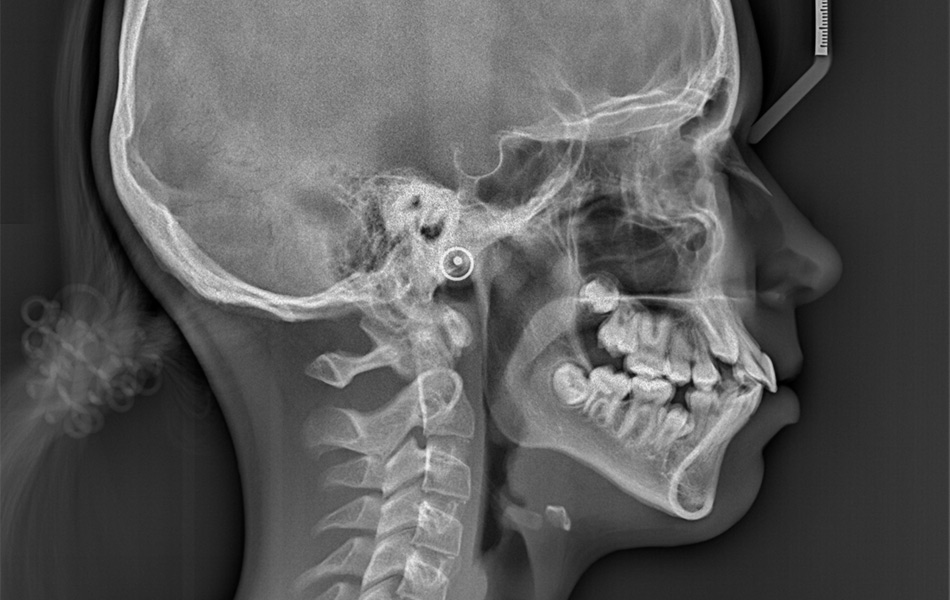

- Рентгеновские снимки (КТ, ОПТГ) суставов с описанием.

В стоматологии 32Дентал диагностика заболеваний височно-нижнечелюстного сустава проходит на современном оборудовании. Наш гнатолог проводит:

Это позволяет точно определить причину и составить индивидуальный план. Многие пациенты говорят: «Наконец-то поняли, почему болит голова годами!»